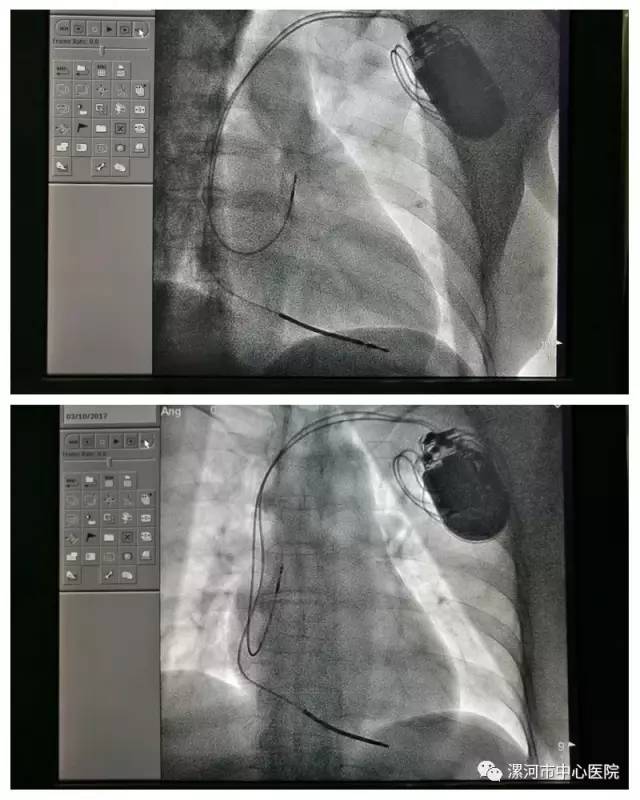

近日,我院(漯河医专一附院)成功为一位频繁发作恶性心律失常患者安装了双腔埋藏式心脏复律除颤器,据了解,此项技术在漯河市首次开展应用。

双腔ICD可以准确识别室上性心律失常,减少误放电等优势,另外该患者动态心电图记录到房性心律失常(排除永久性房颤),有心动过缓诱发的室性快速心律失常(记录到长QT间期伴尖端扭转型室速)病史等证据均提示患者又植入心房电极指征;据2002年ACC/AHA/NASPE及2008年ACC/AHA/HRS指南均描述,如果患者伴有室上性快速心律失常或患者需要双腔起搏治疗,有不适当放电可能性时,均可考虑选择双腔ICD治疗。经过专家团队的充分讨论,最终决定对该患者行双腔埋藏式心脏复律除颤器治疗。

由于该手术为电极植入方式,双腔ICD操作时间更长,手术操作也更为复杂,术前刘东亮主席与董艳彩主任多次咨询相关专家,共同协商,精心制定手术方案,对围手术期可能出现各种突发事件及术中、术后可能出现并发症皆制定详细对策。

手术完成的非常顺利,术后患者病情得到明显好转,出院后生活质量得到极大提高。此次手术的成功实施不仅填补了我市相关领域的技术空白,更标志着我院在恶性心律失常的诊断及治疗方面有了进一步的提升和突破。